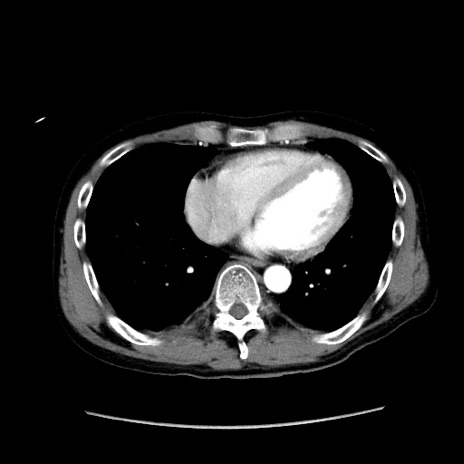

症例37(横断像)

【症例】40歳代 男性

【主訴】腹痛

【現病歴】4時間ほど前に電車に乗車中に臍部上より腹痛出現。徐々に増悪し起立困難となり、救急外来受診。生ものは数日食べていない。今朝お雑煮を食べた。

【身体所見】BT 36.8℃、BP 117/84mmHg、HR 91/min、SpO2 97%、苦悶様、腹部:臍上部広範囲圧痛あり、反跳痛±

【データ】WBC 8100、CRP 0.03